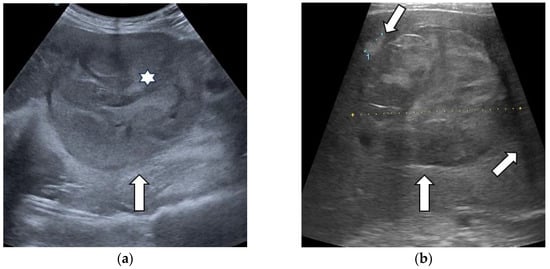

3.1. B-Mode Ultrasound